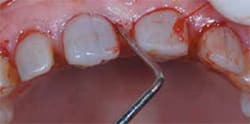

Measurements of sulcular depth, attached gingiva, and bone sounding prior to the surgery (Figure 7) allows for proper formation of biologic width. Gargiulo et al27 reported the biologic width to be, on average, 2.04 mm, with 0.97 mm occupied by junctional epithelium and 1.07 mm occupied by connective tissue attachment to the root surface. Vacek et al28 found 1.34 mm +/- 0.84 mm for sulcus depth; 1.14 mm +/- 0.49 mm for epithelial attachment; 0.77 mm +/- 0.32 mm for connective tissue attachment, and 2.92 mm +/- 1.69 mm for loss of attachment. This supported the concept that the connective tissue attachment is a variable width. However, this is an average and to obtain a precise measurement for a particular patient, bone sounding must be done. If biologic width is violated in a thin biotype, bone loss and gingival recession will occur. In a thick biotype, bone resorption may result in a vertical osseous defect, pocketing, and chronic inflammation.29 Rosenberg30 believed a 6-month wait prior to the final impression was necessary, while Pontiero and Carnevale indicated changes can occur up to 12 months after surgery.31 Two weeks after the initial crown-lengthening procedure, the gingival zenith positions were refined. Chu et al32 found all central incisors have a distal gingival zenith position from the vertical bisected midline of approximately 1 mm, lateral incisors have a slight deviation distal of 0.4 mm, and canines have the gingival zenith position concurrent with the vertical bisected midline, or 0 mm. The gingival zenith level of the lateral incisors is usually 1 mm below a line connecting the gingival zenith level of the adjacent teeth.

Figure 7 Bone sounding prior to crown lengthening to determine where osseous recontouring was required. | Figure 8 Maxillary and mandibular teeth prepared for zirconium crowns and feldspathic porcelain veneers. | ||||||